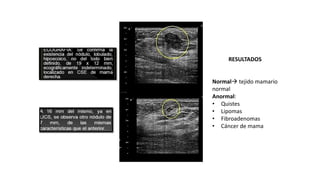

RESULTADOS

Normal tejido mamario

normal

Anormal:

• Quistes

• Lipomas

• Fibroadenomas

• Cáncer de mama